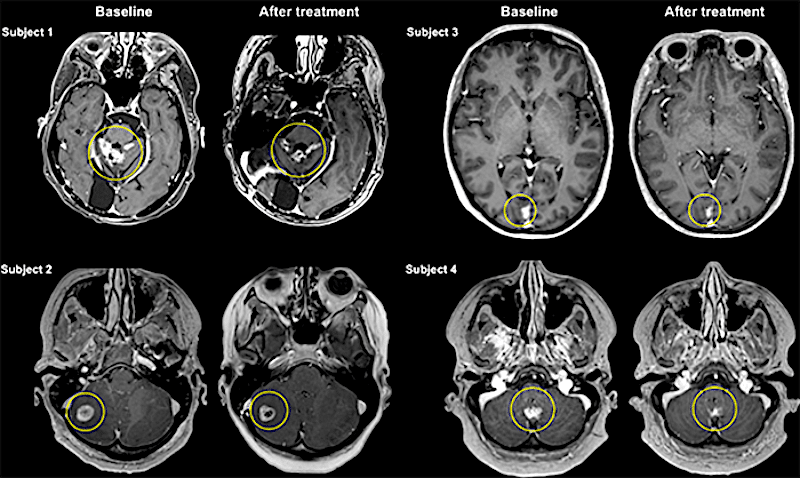

Dans un essai clinique de phase I, quatre femmes atteintes d'un cancer du sein qui s'était propagé au cerveau ont vu leur tumeur réduite par un médicament connu, appelé Herceptin, grâce à cette méthode. Administré seul, il aurait été impossible d'obtenir ce résultat. Cette nouvelle approche se montre donc très prometteuse. Les résultats de l'étude ont été publiés dans la revue Science Translational Medicine.

Après avoir reçu des traitements toutes les trois semaines, jusqu'à six fois, leurs cancers ont diminué de 21% en moyenne. Le médicament avait été marqué avec un composé légèrement radioactif, ce qui a permis de montrer, par IRM, qu'il avait bien atteint leurs tumeurs cérébrales. « La réduction de la taille des tumeurs est prometteuse mais doit être interprétée avec prudence car des recherches supplémentaires à plus grande échelle sont nécessaires », explique le Dr Rossanna Pezo, oncologue médicale au Odette Cancer Centre à Sunnybrook.

Ces résultats ne signifient pas qu'il existe désormais un remède contre les tumeurs cérébrales, car la plupart des cancers avancés finissent par développer une résistance aux médicaments tels que l'Herceptin. Mais le rétrécissement des tumeurs de ces quatre femmes est une preuve de principe que la barrière hémato-encéphalique peut être franchie, déclare James Choi de l'Imperial College London, qui n'a pas participé à l'étude. « Pour moi, c'est le rêve ». Une femme est décédée depuis, en raison de métastase ailleurs dans son corps, mais les autres participantes sont actuellement stables.